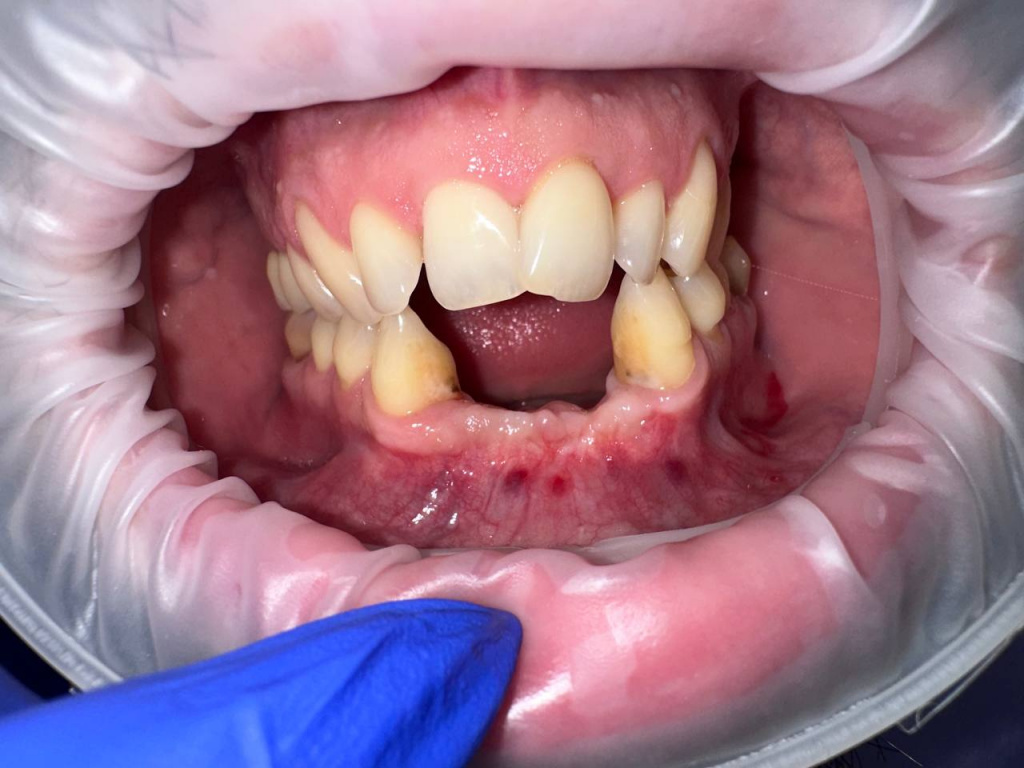

Уже много лет использую в своей практике имплантаты IMPRO. В этот раз мне предоставили линейку IMPRO Respect нового дизайна с широкими лепестками резьбы по отношению к телу имплантата. За счет чего получилось установить имплантаты в переднем отделе в узком гребне и с плохим костным предложением пациента. Ни разу не сталкивалась с осложнениями или проблем с имплантатми IMPRO Implantem. В этот раз не было исключением, была проведена операция через навигационный шаблон, имплантаты стабилизировались с хорошим торком. Хирургический набор и протоколы достаточно просты и удобны. Будем ждать ортопедической части, спустя месяц имплантаты стоят хорошо!

Пациент — мужчина 54 года.